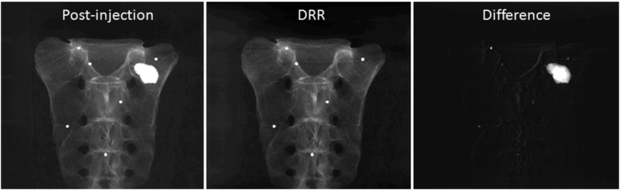

Since we used six beads for registering the CBCT prior volume to the post-injection x-ray projections and there is no soft tissue in the phantom, the registration was very accurate and the difference images clearly show the region of change while other structures are eliminated as shown in figure 3. The VOCs reconstructed from 15, 30, 45, 60 difference images by the PL reconstruction method with different β values (101–1010) were compared to the CBCT ground truth, and figure 4 shows the similarity measure plots as a function of β. It is observed that the reconstruction is noisier at lower β where the estimate is closer to ML estimate, but becomes smoother at higher β where the reconstruction is more regularized by the penalty. Since the shape and structure of the bone cement was not so complicated and the registration was accurate, the overall reconstruction quality was not degraded even when we reduced the number of images and the similarity plots show similar reconstruction performance regardless of the number of images. It is also observed from these plots that the overall reconstruction quality is lower at lower β because it is noisier, but is similarly good when β becomes large. Figure 5 shows an example of slice images of the VOC reconstruction computed from 15 projections after 100 iterations with β = 107 (chosen from figure 4) and its fusion with the prior volume. The reconstructed VOC with prior volume showed significantly reduced artefact compared to the FBP reconstruction (Feldkamp et al 1984) computed from the same 15 post-injection x-ray images.

Figure 3. Example projection images (log-transformed). (Left) X-ray image after the bone cement injection. (Middle) DRR generated from the registered prior CBCT. (Right) Difference image computed by subtracting the DRR from the post-injection x-ray image.